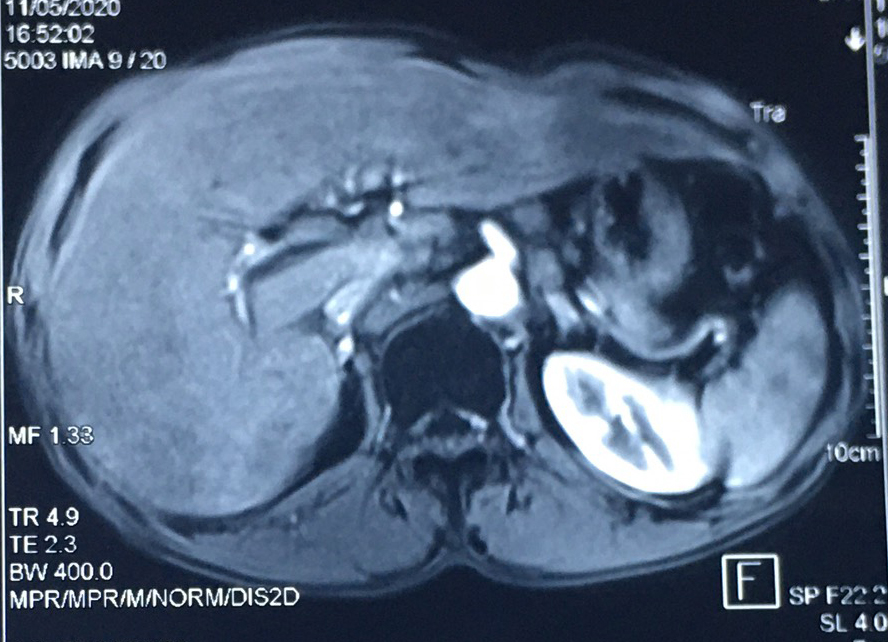

Tại Bệnh viện Ung Bướu Hà Nội, các kết quả cận lâm sàng cho thấy dày thành thực quản 1/3 dưới tạo khối kích thước 5x2.5cm, thâm nhiễm mỡ xung quanh, có nhiều hạch quanh tổn thương, kích thước hạch lớn nhất 2 cm. Đáng nói, ung thư đã di căn gan với ổ lớn nhất đường kính 3 cm. Tại giai đoạn này, các biện pháp điều trị tại chỗ, tại vùng không còn khả thi. Bệnh nhân được chỉ định điều trị hóa chất toàn thân.

Ảnh 1: Hình ảnh di căn gan trước và sau điều trị

Sau chu kỳ đầu tiên, bệnh nhân đáp ứng thuốc và đã có thể nuốt thức ăn. Kết thúc 4 lần truyền, bệnh nhân ăn tốt, tăng cân, đáng mừng hơn là kết quả xét nghiệm không còn thấy tổn thương di căn gan.